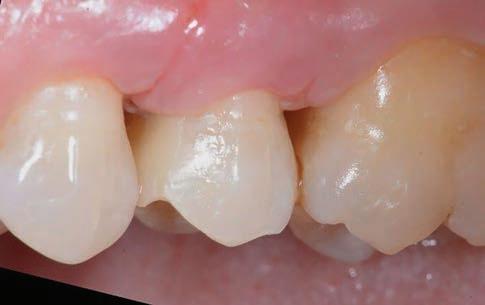

At the end of the procedures, the restoration was precisely seated at equigingival level of the margins, it appeared to be morphologically integrated in the dental arch, with correct contact points and with a good chromatic match with the adjacent elements (Figs. 21-24). Upon X-ray examination, it was possible to see that the subgingival margins were also integrated, without any step or any plaque-retaining area that could be a problem for the home dental hygiene (Fig. 25). The patient didn’t refer pain anymore and was completely satisfied with the prosthetic rehabilitation, that she found perfectly integrated at both functional and chromatic levels. She also found the colour of the prosthesis was better than her natural teeth.

Figure 23: Final occlusal view. Figure 24: Final occlusal view at higher magnification.